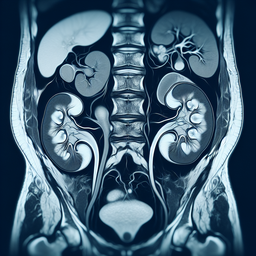

МРТ урографія

МРТ урографія — це неінвазивний метод діагностики сечовидільної системи, що використовує магнітно-резонансний томограф для створення детальних зображень нирок, сечоводів і сечового міхура.